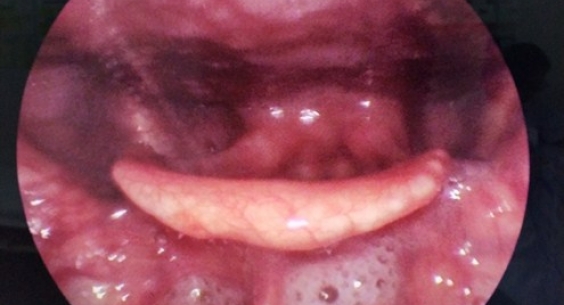

ThS.BS Trần Hữu Thắng - Trưởng khoa Cấp cứu, Bệnh viện Tai Mũi Họng Trung ương cho biết, bệnh nhân Nguyễn Văn T. (52 tuổi, quê ở Tiền Hải, Thái Bình) nhập viện ngày 14/5/2019 trong tình trạng tỉnh, tiếp xúc được, nhưng khó quay cổ vì đau. Da, niêm mạc vẫn hồng hào, khám hạch ngoại biên không thấy, tuyến giáp không to.